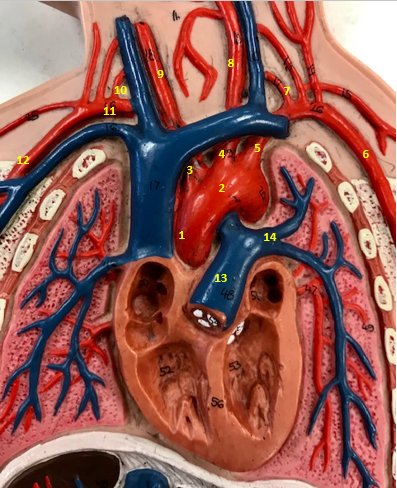

Aorta

Name #2

Brings blood out of left ventricle

Function of aorta

Brachiocephalic artery

Name #3

Supplies oxygenated blood to right arm shoulder neck and head

Function of brachiocephalic artery

Left common carotid artery

Name #4

Supplies oxygenated blood to left neck and head

Function of left common carotid artery

Left subclavian artery

Name #5

Supplies oxygenated blood to left arm shoulder

Function of left subclavian artery

Left axillery artery

Name #6

supplies blood to left armpit and upper limb

Function left axillary artery (6)

Left vertebral artery

Name #7

Supplies blood to brain and spinal cord

Function of left vertebral artery (7)

Left common carotid artery

Name #8

Supplies blood to left neck and head

Function of left common carotid artery (8)

Right common carotid artery

Name #9

Supplies oxygenated blood to right neck and head

Function of right common carotid artery (9)

Right vertebral artery

Name #10

Supplies blood to brain and spinal cord

Function of right vertebral artery (10)

Right subclavian artery

Name #11

Supplies blood to right arm and shoulder

Function of right subclavian artery

Right axillery artery

Name #12

Supplies blood to right armpit and upper limb

Function of right axillery artery (12)

Pulmonary trunk

Name #13

Bring blood out of right ventricle to lungs

Function of pulmonary trunk (13)

Left pulmonary artery

Name #14

Bring blood to left lung

Function of left pulmonary artery (14)